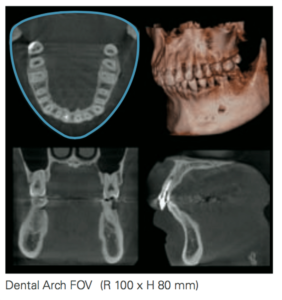

Dental Arc FOV (R 100 x H 80mm)